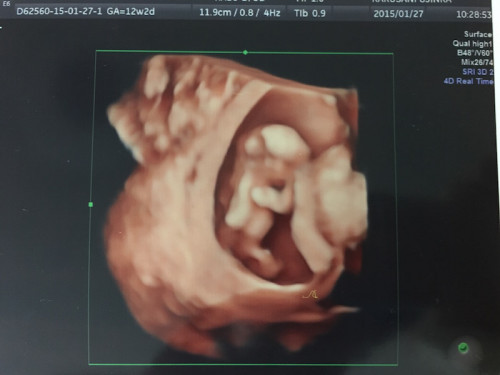

2人目の出産の際に通っていた産院で、最新技術の“HDライブ”でお腹の赤ちゃんを撮影してもらったことがあります(上写真)。3D、4Dよりもさらにリアルに、内視鏡画像のように表現できる画期的な技術だそう。12週の時の様子です。立体的ですよね!